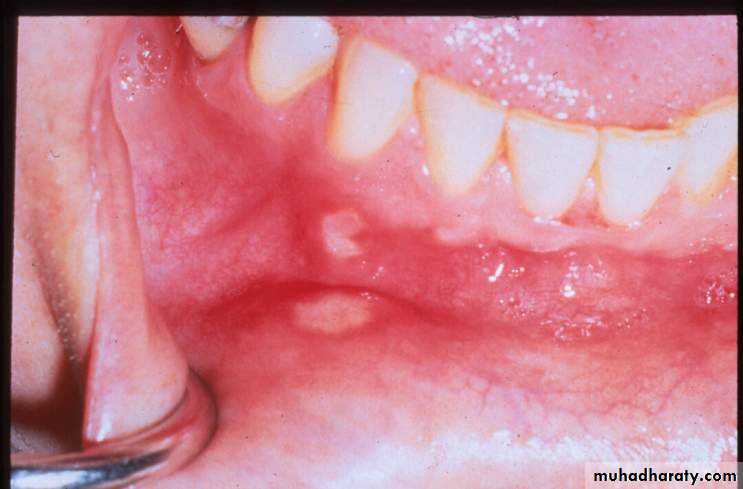

Recurrent Aphthous Stomatitis

Clinical features• – Affects mobile mucosa

• – Most common oral ulcerative condition

• – Three forms

• »Minor

• »Major

• » Herpetiform

Minor Aphthae

• »Most common

• » Small, shallow ulcerations with slightly raised erythematous borders

• » Central area covered by yellow-white pseudomembrane

• » Heals without scarring in 10 –14 days

Minor Apthae